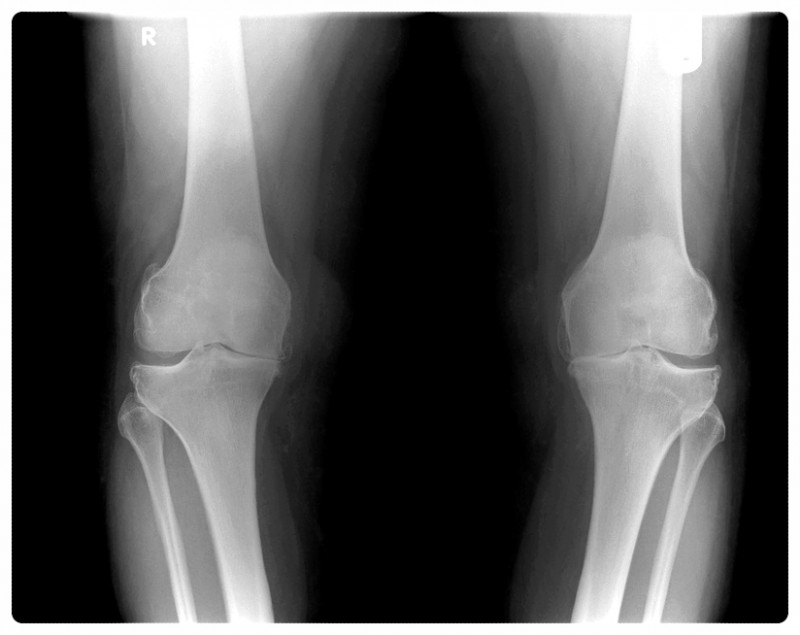

Q. 연골이 닳아서만 아픈 게 아니라고요?

무릎 통증이 있으면 가장 먼저 연골 문제를 떠올리시는 분들이 많습니다.

물론 연골은 중요한 요소입니다.

다만 제가 바라보는 관점은 조금 다릅니다.

무릎 통증의 핵심 원인은

관절이 틀어진 상태로 오랜 기간 사용되었기 때문인 경우가 많다고 보고 있습니다.

관절 정렬이 흐트러진 상태에서는 특정 부위에 압력이 반복적으로 집중되고,

그 결과 연골과 주변 조직에 부담이 쌓이게 됩니다.

즉, 연골이 닳아 보이는 결과가 나타나긴 하지만

문제의 시작이 항상 연골 자체는 아닐 수 있다는 이야기입니다.